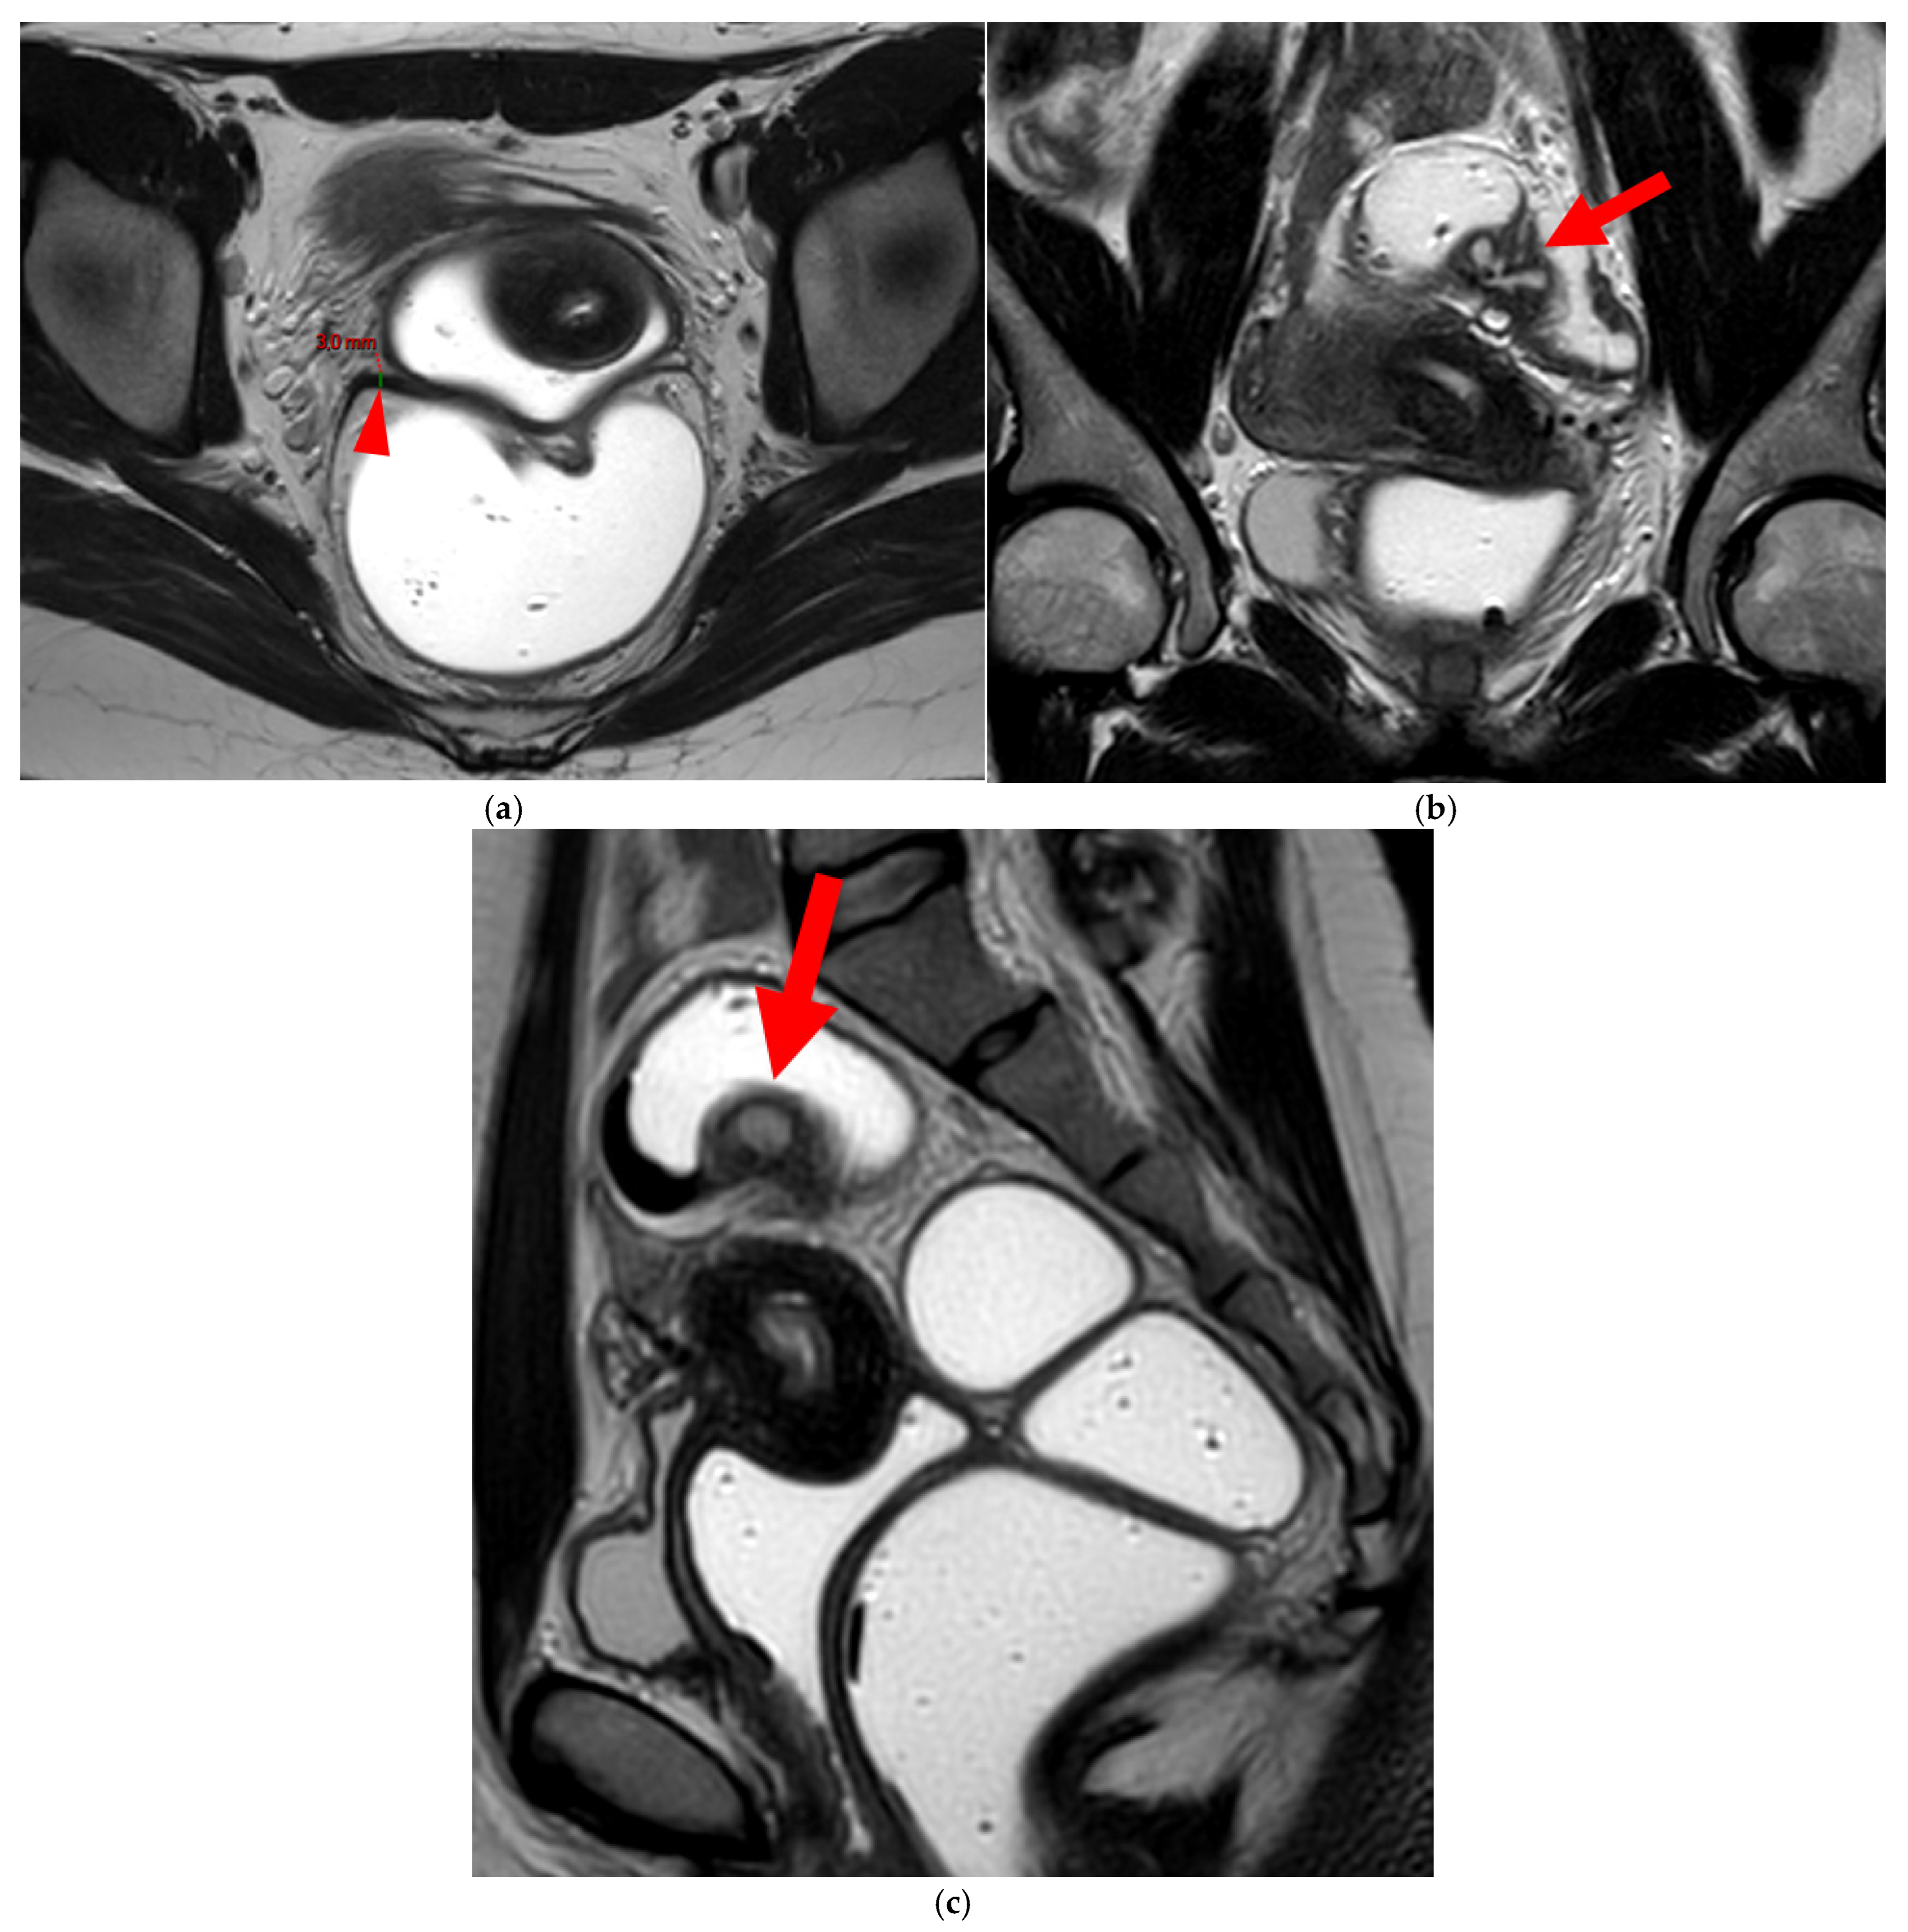

A type 3B USL (Figure 4), in addition to being thickened, has a notched surface with slightly irregular margins, or a caliber disparity with focal thickening, or appears “stiffened”, which means it loses its curvilinearity to exhibit a steep vertical orientation in the sagittal plane or a “bowstringing” of the USL in the sagittal or axial planes. Occasionally, a USL might appear thin but “stiffened”, which would upgrade it from a type 2 to a type 3B.

Figure 4. Pelvic MRI scans of seven patients with HTD type 3B USLs. (a) Sagittal T2WI: a thickened (2.1 mm) and stiffened right USL (arrowhead) with “bowstringing”. (b) Axial T2WI: a caliber disparity (dashed arrows) with focal thickening (4.2 mm) of the left proximal USL (arrowhead). (c) Sagittal T2WI: a caliber disparity (dashed arrows) with focal thickening (2.5 mm) of the right distal USL. (d) Axial T2WI: a right USL with a notched and irregular surface (dashed arrows). (e) Axial T2WI: thickened and stiffened left (3 mm) and right (2.5 mm) USLs with “bowstringing” of both USLs (arrowheads). (f) Sagittal T2WI: a thickened (2.6 mm) right USL with a stiffened appearance characterized by a steep vertical orientation (arrowhead). (g) Sagittal T2WI: the right USL appears thin (1.9 mm) but stiffened (arrowhead), exhibiting “bowstringing”. These findings led to its reclassification from type 2 to type 3B.